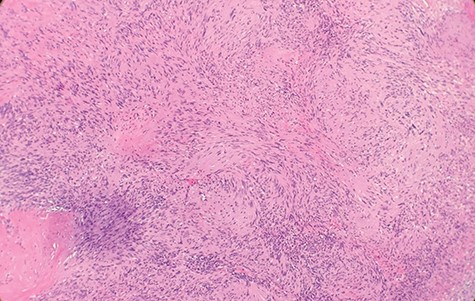

Macroscopically, the tumor appeared encapsulated, rubbery and pink-tan in color. Microscopic examination reveals that tumor composed of biphasic spindle hypercellular Antoni A areas and hypocellular Antoni B areas (Fig. 1). Higher magnification reveals that spindle tumor cells are narrow, elongate, wavy with tapered ends interspersed with collagen fibers (Fig. 2). Immunohistochemical staining revealed that most tumor cells reacted strongly for S-100 protein (Fig. 3). Combined with immunohistochemical profile, these histological features are diagnostic of benign schwannoma. Patient was discharged home on the same day as the operation. At the 1-month follow-up, he was symptom free, without any pain or sensory disturbances.

Higher magnification reveals spindle tumor cells are narrow, elongate, wavy with tapered ends interspersed with collagen fibers (×20).